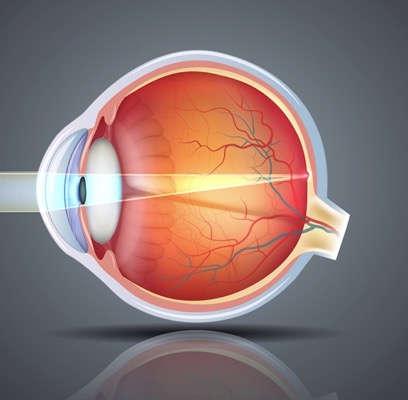

КТ-графики и изображение строения глаза